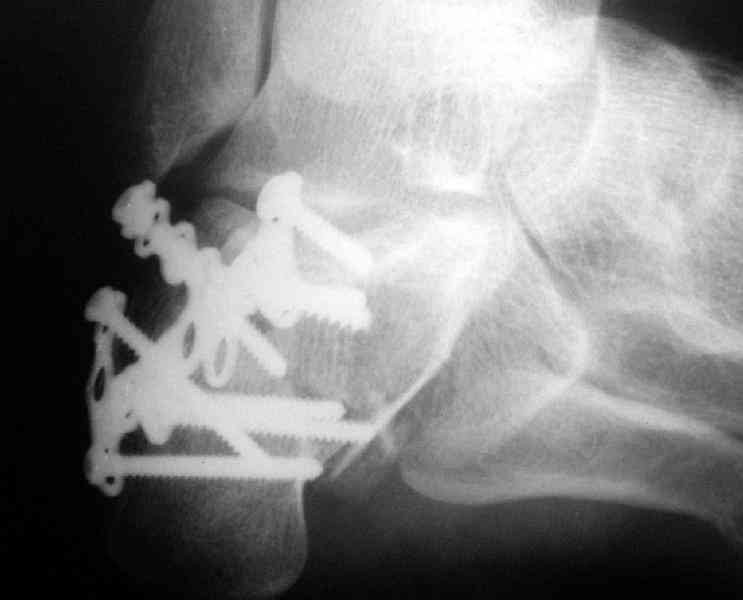

Re: Перелом пяточной кости

Открытый и закрытый способы лечения.